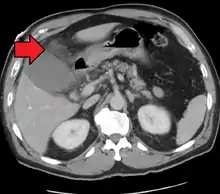

| Acute cholecystitis as seen on CT. Note the fat stranding around the enlarged gallbladder. | |

Acute cholecystitis with gallbladder wall thickening, a large gallstone, and a large gallbladder- Significant gallbladder wall thickening[29]

- Significant gallbladder wall thickening[29]